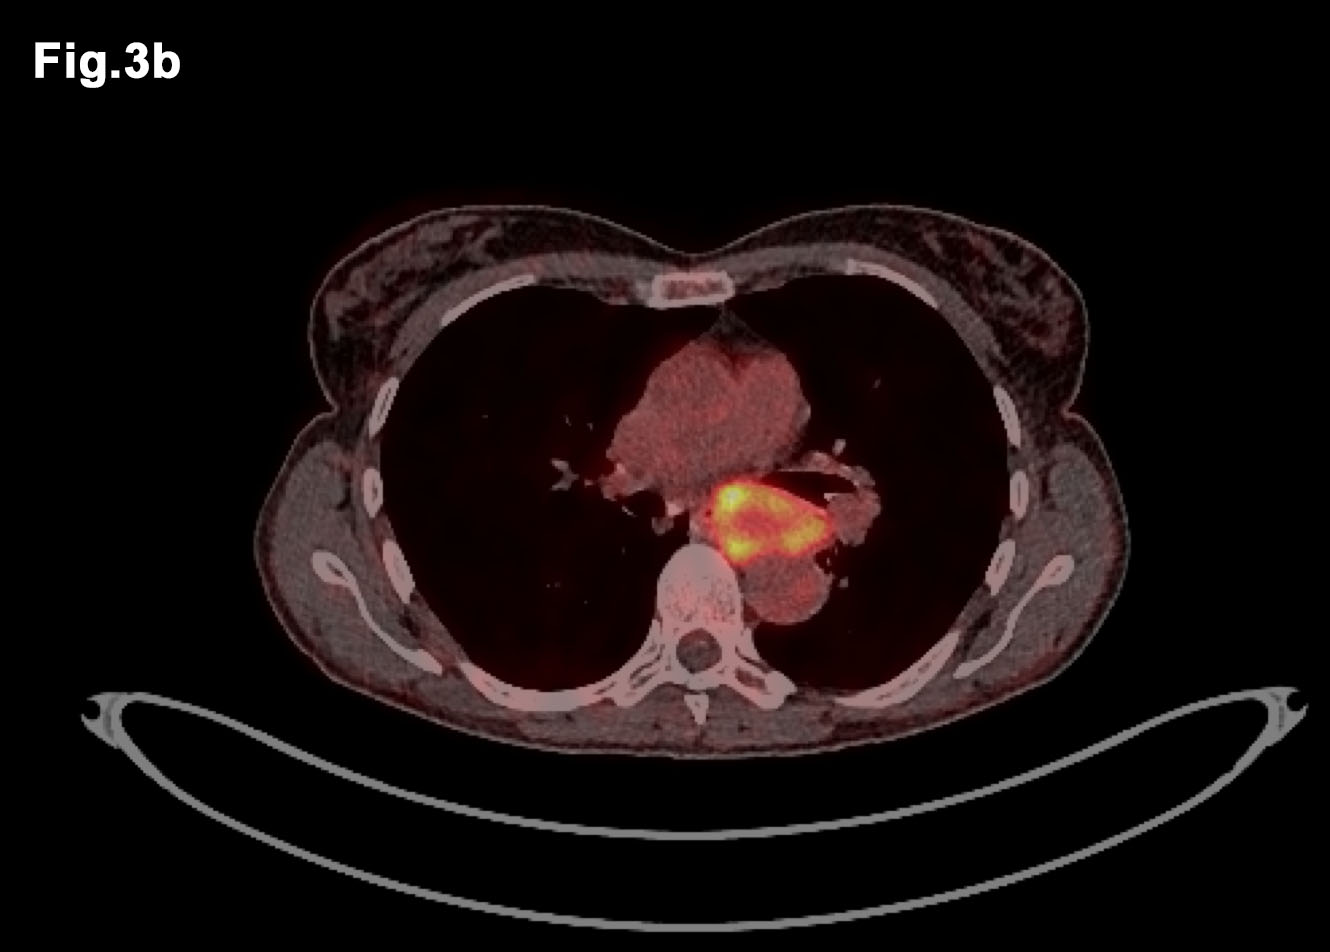

Figure 3 – PETCT images demonstrate avid lesions in both thighs (a) and further avid lesion in posterior mediastinum (b) - PET CT images of both legs demonstrate avid FDG take up in right and left lesions (Fig 3a) - ET CT showing Mediastinal primary tumour which also demonstrates FDG avidity (Fig 3b)

- PET/CT Sep 2016 (Figure 3)

- FDG acid lesions seen in both thighs and within posterior mediastinum